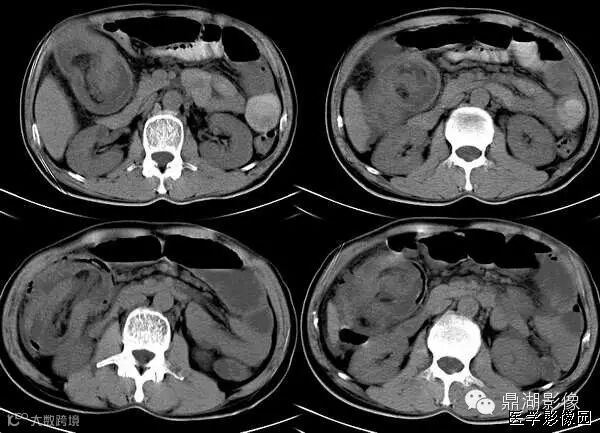

1靶征(肠套叠)

是肠套叠最常见的特征性CT征像,为肠套叠长轴与CT扫描层面垂直时的表现,反映了套叠的各层肠壁、肠腔及肠系膜间的关系。典型排列为自外向内分别代表鞘部外层肠壁、鞘部肠腔内造影剂、鞘部内层肠壁、偏心性套入部肠系膜、套入部肠壁、套入部肠腔内造影剂。

由于肠套叠长轴与CT扫描层面的角度不同,表现各异。如扫描层面和迂曲的肠道相平行时,表现为彗星尾征或肾形征:即套叠近端肠系膜血管牵拉聚拢的征象。一般情况下,彗星尾征均与肾形肿块相伴出现。该肾形肿块为套鞘部游离缘与套入部近端肠管及肠系膜的CT斜切面图像,其中游离的套鞘呈弧形围绕套入部,形状若肾轮廓外形,而套入部近端肠管、肠系膜形状若肾蒂。此时,所谓彗星尾征的组成还应包括套入近端肠管。如果套叠的肠管与CT扫描垂直,则呈靶形征,即肿块影表现为圆形或类似环形。通常在肿块内可分辨出层样结构,推测可能是继发于套入部和鞘部间的液体或是肠壁水肿造成密度对比,类似同心圆形;当套入部肠壁显著水肿坏死或套入部肿瘤周围浸润累及肠系膜,肠系膜血管及脂肪、套叠时间较长,套入部系膜血管受挤压时,静脉血液回流障碍,套入部肠壁充血水肿、变硬,形成不完全性肠梗阻,套叠以上肠管蠕动增强,可引起代偿性肠管扩张肥厚,并可见肠系膜连同其血管纠集、扭曲,形成“漩涡征”。